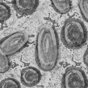

Lengyelországban is felbukkant a majomhimlő, az első kimutatott esetről Adam Niedzielski egészségügyi miniszter számolt be pénteken.

Eddig 10 vírusgyanús esetet vizsgáltak Lengyelországban, az első fertőzést pénteken erősítették meg - közölte Niedzielski a közép-lengyelországi Lódz város orvosi egyetemén rendezett sajtóértekezleten.

A lengyel sajtó az Egészségügyi Világszervezet (WHO) szerdán ismertetett adatait idézi, amelyek szerint már több, mint ezer majomhimlős esetet regisztráltak olyan országokban, ahol a vírus nem honos. A közép- és nyugat-afrikai térségen kívül a fertőzés 29 országban bukkant fel, senki nem halt meg a szövődményekben.